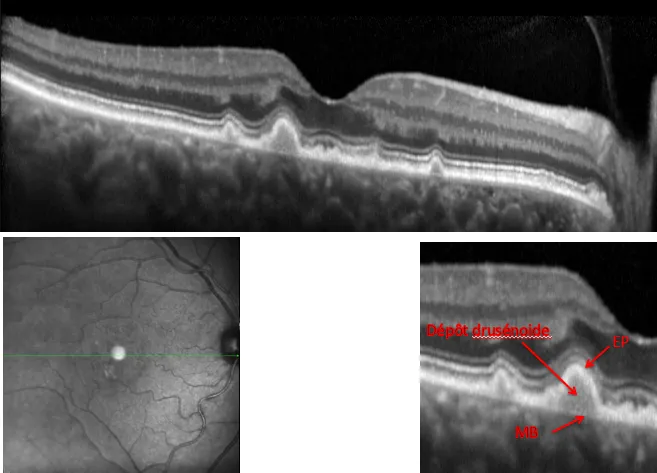

3.DMLA: Coalescence des Drusen et DEP Drusénoïde

• C'est le stade précurseur de la DMLA qui se caractérise par l'apparition de fins dépôts amorphes dans la rétine aux deux yeux, appelés "Drusen", pouvant s'associer à quelques anomalies de la pigmentation rétinienne.

• Les dépots dans la rétine sont plus nombreux et de plus grandes tailles(Drusen séreux)

• Ces dépôt peuvent être confluents , coalescents et s'associer à des anomalies de la pigmentation rétinienne